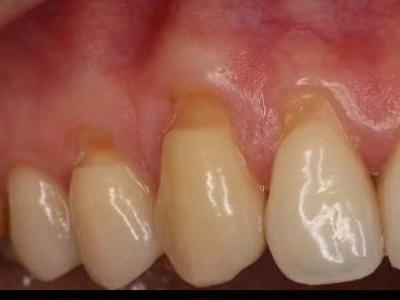

Опустились дёсны в нескольких местах, обнажились шейки зубов. Чувствительные, болят от прикосновений, могут реагировать на холодное, горячее, сладкое.

Ситуация как примерно на пик2.

2) Простое заделывание чувствительных мест пломбой/аналогом пломбы без пластики дёсен.